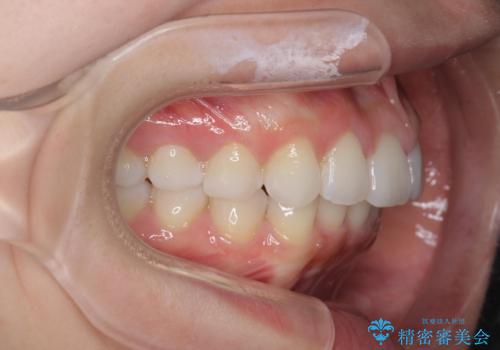

前歯のがたつき気になる。インビザラインモデレート

- 前歯のがたつきが気になるとの事で来院。

噛み合わせを確認したところ上の歯が全体的に前にある状態でした。

患者様は2のプランを選ばれたのでインビザラインモデレートで治療を行いました。

ガタつきがなくなり満足して頂けました。